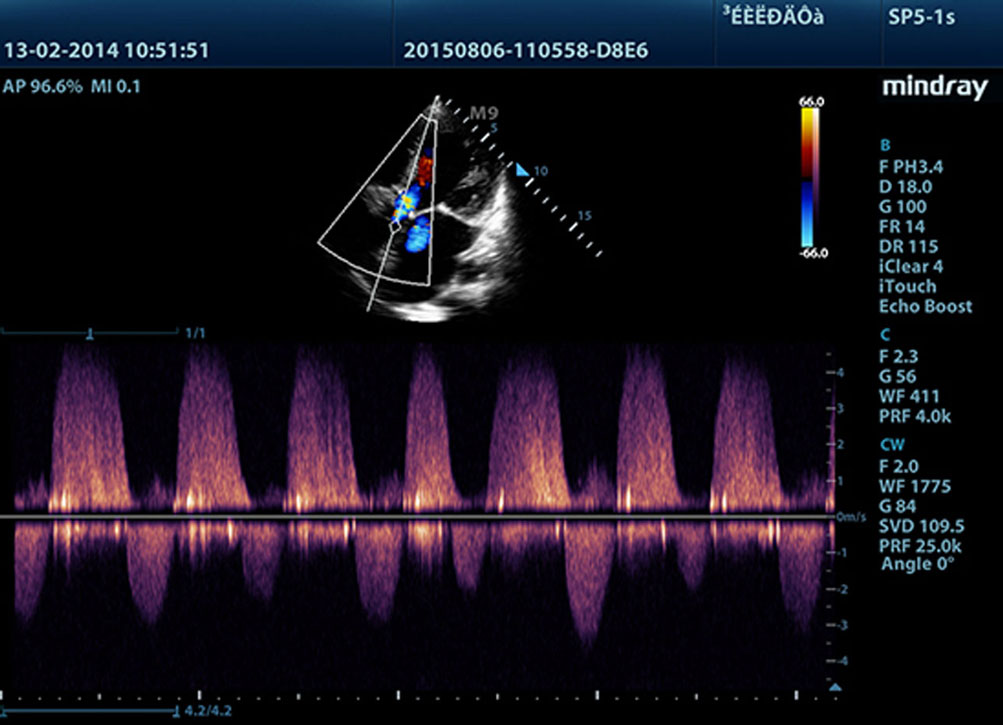

Berbasis mQuadro, yakni platform ultrasound generasi terbaru Mindray, M9 telah menaikkan standar industri ke level baru. Prosesor transmisi dan penerimaan sinyal canggih memungkinkan deteksi gema yang sangat sensitif dan akurat. Teknologi transduser inovatif menghasilkan penetrasi yang lebih baik dan resolusi lebih tinggi serta dan meningkatkan kemampuan diagnosis.

Menampilkan gambar yang lebih tajam, semua jarum yang kompatibel dengan M9 dilengkapi teknologi transduser 3T Mindray yang unik. Disempurnakan dengan penambahan teknologi kristal tunggal, M9 menawarkan penetrasi dan aliran dinamis warna yang lebih baik, terutama selama pemindaian pasien yang sulit dilakukan.

Teknologi pemrosesan sinyal adaptif Mindray yang unik dengan deteksi gema pintar, dirancang agar menggunakan informasi sinyal-ke-noise asli untuk menyempurnakan sinyal gema yang lemah sekaligus mengurangi suara bising di sekitar. Dengan demikian, dapat dihasilkan kecerahan gambar yang lebih seimbang dan visualisasi lapisan jaringan miokardium yang lebih baik.